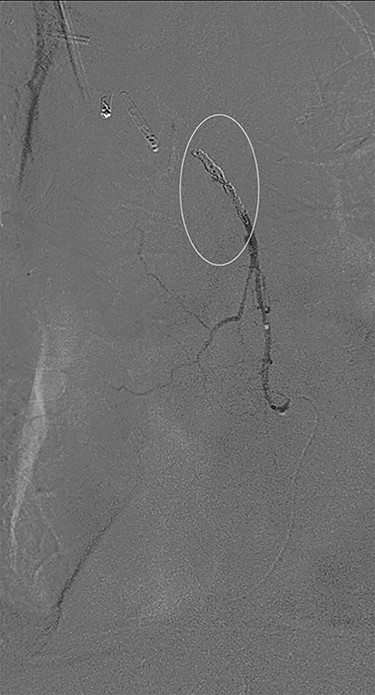

Successful coil embolization of the terminal portion of the gastro-epiploic arcade. Ellipse = coil.

Eight days later, he represented with an upper gastrointestinal bleed with massive haematemesis requiring immediate intubation for airway protection. Computer tomography angiography was unremarkable and an emergency gastroscopy revealed an extensive amount of blood and clot in the oesophagus and gastric conduit (limiting the view), but no active bleeding point. Conservative treatment in the Intensive Care Unit (ICU) with blood transfusion, proton pump inhibitors and life support were implemented. Another large bleed occurred 2 days later and a repeat gastroscopy revealed a non-bleeding visible vessel at the OG anastomosis and a haemostatic clip was applied. However, over the next 10 days, the patient remained blood transfusion dependent and had two further endoscopies. The first was unremarkable, but the second endoscopy re-demonstrated the luminal vessel at the OG anastomosis, with no evidence of the previously placed clip. This was felt to be the cause of his intermittent and problematic bleeding, so another haemostatic clip was attempted, resulting in pulsatile, moderate volume arterial bleeding. The procedure was abandoned and the patient transported immediately to the Interventional Radiology Suite. Right femoral access was obtained and angiography performed. The thoracic aorta was normal, so the celiac trunk was cannulated and angiography of the right gastro-epiploic artery performed (Fig. 1), revealing active extravasation of contrast at the OG anastomosis as shown in Fig. 2. A microcatheter was advanced along the length of the right gastro-epiploic artery to the OG anastomosis and coil embolization was performed (Fig. 3). Care had to be taken to ensure that the embolization was as distal as possible to limit the risk of ischaemic complications. The patient required lengthy ongoing care in the ICU for organ dysfunction but remained hemodynamically stable after embolization without evidence of conduit ischaemia. His hospital stay was obviously lengthy, but he was ultimately transferred to a rehabilitation unit.